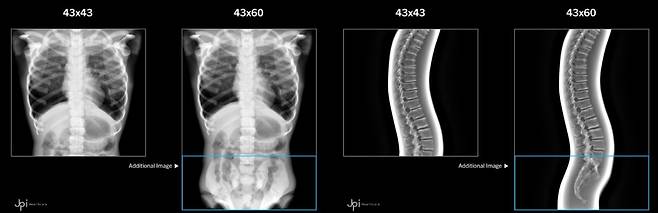

토모신세시스는 엑스선과 CT(컴퓨터 단층 촬영) 중간 단계에 해당하는 영상장비다. 흉부와 복부, 옆구리, 관절, 두개골 같은 신체 부위를 촬영한다. 엑스선은 인체 내부를 2차원으로 보여주지만 토모신세시스는 3차원 영상을 제공해 의료진이 질병을 발견하기 쉽다.

CT는 인체를 수백 장의 고해상도 평면 엑스선 영상으로 나눠 찍는방식이다. 각각의 엑스선 영상은 조직 단면을 보여준다. 이를 모으면 인체 내부를 입체로 볼 수 있다. 토모신세시스는 엑스선을 여러 각도에서 찍어 CT처럼 입체 영상을 얻는 방식이다. 엑스선 촬영이 적어 CT보다 방사선 노출도 줄어든다.

회사는 독자 기술로 이른바 ‘방사선 딜레마’를 해결했다. 인체에 방사선을 많이 쏘면 화면은 선명하지만 그만큼 피폭량도 늘어난다. 방사선을 줄이면 화면이 흐릿해진다. 회사는 그리드로 문제를 해결했다. 그리드는 가로 43㎝, 세로 60㎝ 네모난 판처럼 생긴 부품으로, 토모신세시스 디텍터(반사판)에 끼워 사용한다. 디텍터는 방사선으로 촬영한 영상을 사람의 눈으로 볼 수 있게 바꿔주는 부품이다.

김 대표는 “엑스선이 신체를 통과할 때 각종 뼈와 조직에 부딪혀 여러 갈래로 튕겨간다”면서 “그리드가 불필요한 산란(散亂)을 제거해 화면이 왜곡되는 노이즈를 줄이고 선명도를 높였다”고 했다. 회사는 납과 알루미늄을 넣어 반도체 제조 공법으로 그리드를 만들었다. 방사선 피폭은 줄이고 투과력은 높여 인체 내부 화면을 자세하게 구성했다.